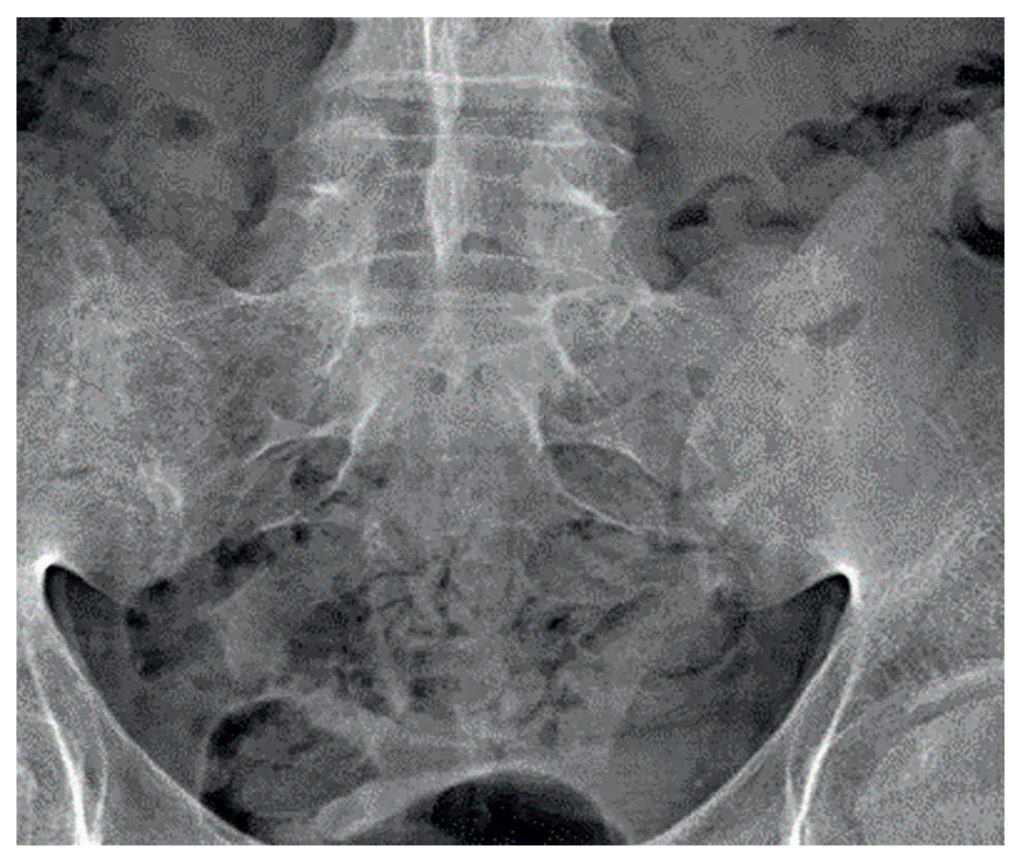

Recent investigations showed normal full blood count, renal and liver profile with a raised CRP of 10mg/L, and erythrocyte sedimentation rate (ESR) of 21mm/hr. HLA-B27 was positive. On a review of previous pelvic x-rays, radiographic progression can be seen between 2007 (Figure 1), showing SIJ joint widening, and 2015 (Figure 2), showing SIJ sclerosis and erosions, and 2023 showing bilateral SIJ fusion (Figure 3).

Figure 1: SIJ x-ray in 2007 showing SIJ widening and early changes of sacroiliitis | Figure 2: SIJ x-ray in 2015 showing bilateral sclerosis and erosions | Figure 3: SIJ x-ray in 2023 showing bilateral ankylosis